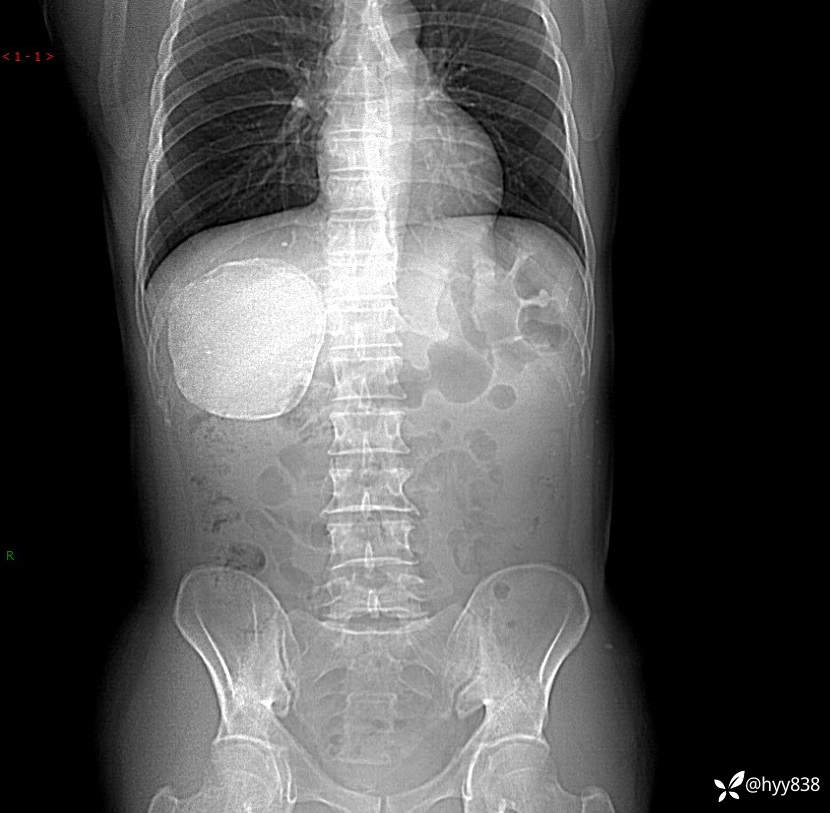

性别:男

年龄:50岁

简要病史:夜尿增多半月,发现肾功能异常1天,超声发现腹膜后占位

腹部CT平扫+增强